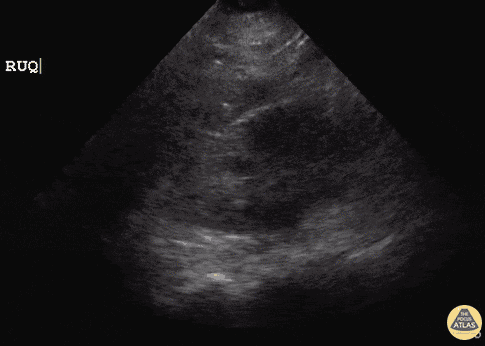

Pediatrics - Hydronephrosis (Mild)

21 y/o female post-op emergency hysterectomy post uterine rupture with rising creatinine in surgical ICU. POCUS revealed right-sided mild Grade I hydronephrosis with appreciable dilated major calyces and renal pelvis. Initial concern is for obstructive process or ureter injury. Dr. Sathya Subramaniam, Pediatric EM Fellow - Kings County/SUNY Downstate